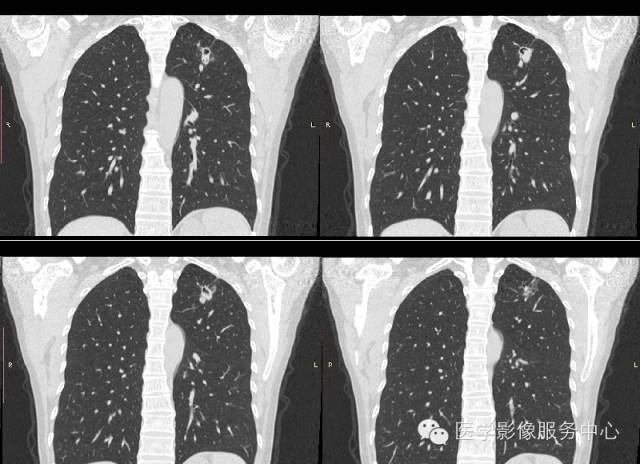

【病例】肺曲菌病1例CT影像表现

女,42岁,间断性咯血一年。

1、肺部炎症样改变:CT表现为胸膜下楔形、不规则片状致密影,边缘模糊,可累及多个肺叶及肺段,可与结节灶同时存在。胸膜下楔形实变影对曲菌病的诊断有重要价值,与其出血性肺梗死的表现一致。

2、单发或多发结节:大多位于肺的中外带,结节大小不一,在CT图像上,其边缘可见略低于结节密度而又高于肺实质的环形“磨玻璃”样改变,称为“晕征”或“环征”。结节 晕征是肺曲菌病较特征的早期表现。CT检查可发现早期肺内较小的结节影。肿块样浸润指病灶直径大于3cm的软组织块影,无分叶及毛刺,周围可出现“晕征”。

3、曲菌球:一般寄生在肺部慢性疾病所致的空洞或空腔内,常见的有结核空洞、支气管扩张、先天性肺囊肿等。空洞大小不等、洞壁薄厚不一,其内曲菌球一般呈圆形或卵圆形,密度均匀,边界光整,在洞内处于游离状态,可随体位改变而移动,曲菌球与洞壁之问形成一新月形的含气腔隙。曲菌球具有特征性的诊断价值。